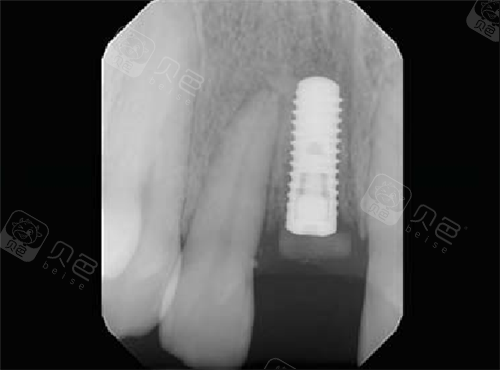

瑞士ITI种植体

瑞士士卓曼iti种植牙植入后

瑞士士卓曼iti亲水型种植牙